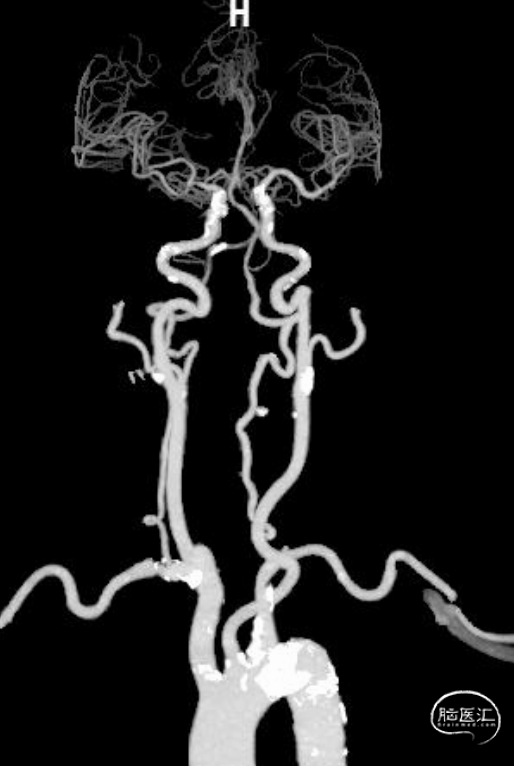

CTA